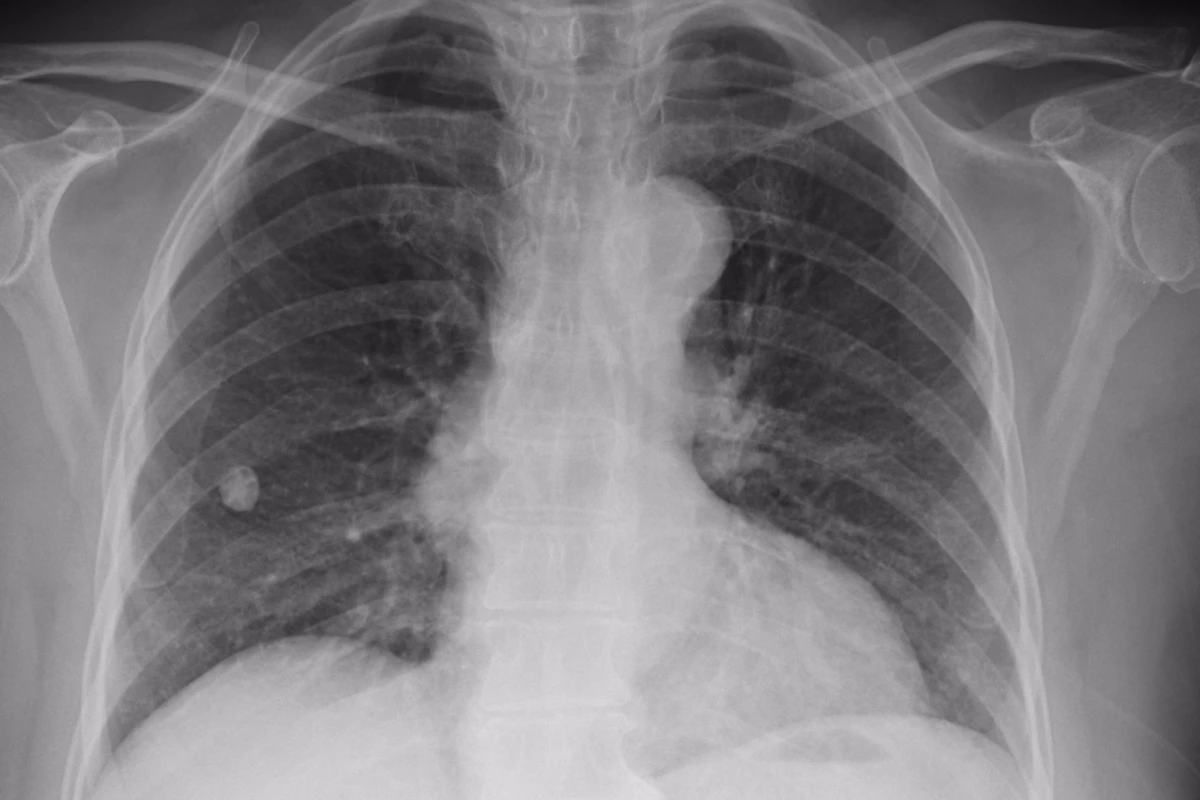

Chinese radiologists look at hundreds of medical images every day. Infervision hopes to use AI and deep learning to dramatically speed up the repetitive work of detecting lung cancer in its early stages

It seems we can add medical imaging to the list of fields about to be revolutionized by artificial intelligence and deep learning computers. A Chinese startup called Infervision has revealed that its intelligent assisted diagnosis software for X-Ray and CT scans has already looked at over 200,000 scans in trials at 20 hospitals around China.

Predominantly used in early-stage lung cancer screening, the system started out with a huge stock of digital health records dating back to 2003 and employed technologies from GE Healthcare, Nvidia and Cisco, as well as more than 50 deep learning algorithms, to refine its diagnosis techniques into a tool it calls AI Scholar.

According to China's Toutiao news site, the Infervision system triples the speed at which radiologists can diagnose CT scans, and has helped reduce the rate of missed cancer diagnoses by some 50 percent.

The company's goal is not to replace doctors or radiologists, but to help them get through what's starting to look like an insurmountable workload. According to Weixin, the amount of medical imaging data is growing by 30 percent per year in China, while the number of radiologists is growing by 4.1 percent, leading to 14-hour work days and stressed out workers.

An AI diagnostic tool that's constantly learning and refining its abilities could cut way down on the repetitive work of trawling through scans, chewing through over 100 high-definition Dicom medical images per second, and letting doctors get to more people.